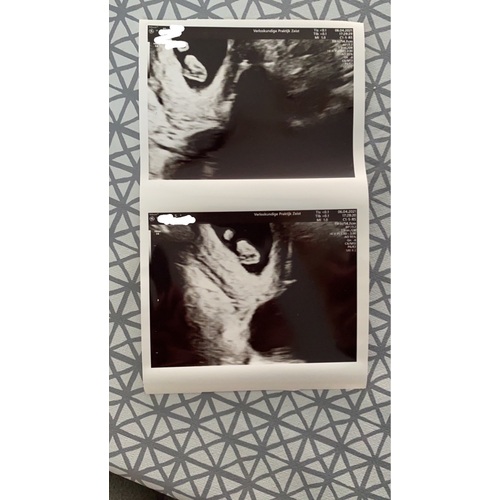

Ja, dit nieuws kreeg ik vandaag ook bij mijn eerste echo. Bleek een vrij grote te zijn, dus mag niet springen, rennen, sporten en moet voorzichtig doen met seks. Gaat als het goed is vanzelf weer over zei de arts. Vind het wel een beetje een spannend idee dat die cyste daar zo zit.🙈

Ik had hetzelfde gister bij mijn eerste echo. 7+3. ze noemde het een overblijfsel van de eiersprong. Het eitje knapt als het ware en daar blijft een holte achter die zich vervolgens vult met vocht. Ze zei dat het waarschijnlijk zal verdwijnen en dat er de volgende echo even naar gekeken wordt.